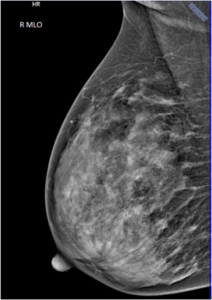

43 year female patient has come for routine screening mammogram.